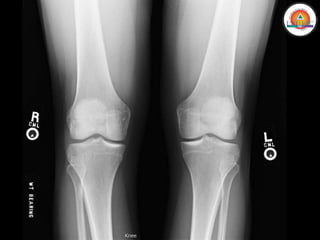

MIEMBRO INFERIOR

• Rodilla

• Pierna (Tibia y Peroné)

• Rótula

• Tibia

• Peroné

MIEMBRO INFERIOR • Cinturapélvica • Cadera • Muslo (Fémur) • Rodilla • Pierna (Tibia y Peroné) • Tobillo • Pie (Tarso, Metatarso y Falanges)

MIEMBRO INFERIOR Huesos: • Pelvis •Fémur • Rótula • Tibia • Peroné • Tarso • Metatarso • Falanges